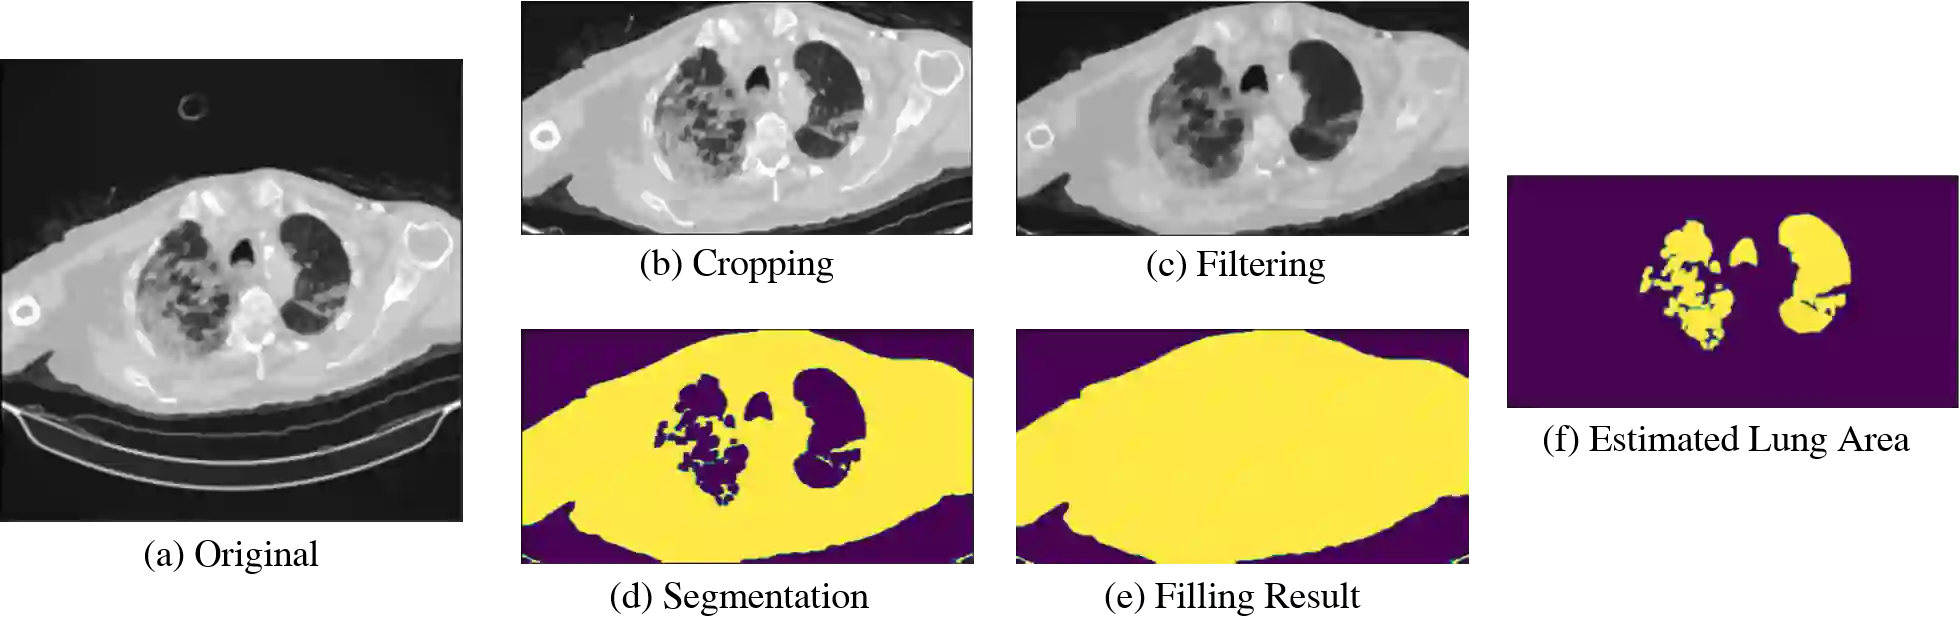

Computed tomography (CT) imaging could be very practical for diagnosing various diseases. However, the nature of the CT images is even more diverse since the resolution and number of the slices of a CT scan are determined by the machine and its settings. Conventional deep learning models are hard to tickle such diverse data since the essential requirement of the deep neural network is the consistent shape of the input data. In this paper, we propose a novel, effective, two-step-wise approach to tickle this issue for COVID-19 symptom classification thoroughly. First, the semantic feature embedding of each slice for a CT scan is extracted by conventional backbone networks. Then, we proposed a long short-term memory (LSTM) and Transformer-based sub-network to deal with temporal feature learning, leading to spatiotemporal feature representation learning. In this fashion, the proposed two-step LSTM model could prevent overfitting, as well as increase performance. Comprehensive experiments reveal that the proposed two-step method not only shows excellent performance but also could be compensated for each other. More specifically, the two-step LSTM model has a lower false-negative rate, while the 2-step Swin model has a lower false-positive rate. In summary, it is suggested that the model ensemble could be adopted for more stable and promising performance in real-world applications.